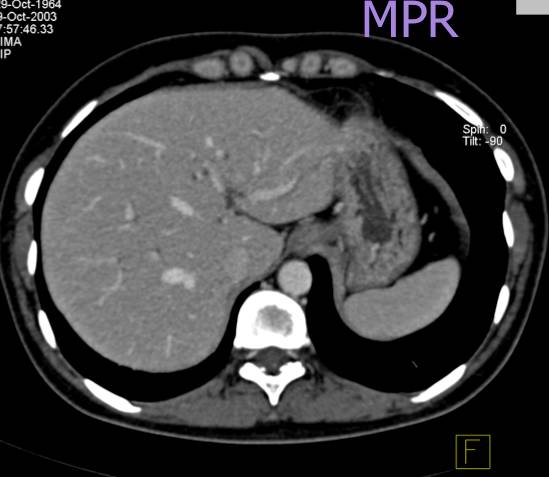

5、MPR(多平面成像):把体素重新排列,在二维屏幕上显示任意方向上的断面。它补偿了CT只提供横断面图像的缺憾,适用于任何需要从多角度、多方位观察的病灶和器官。它有显示快捷、任意断面、CT值可测的好处。